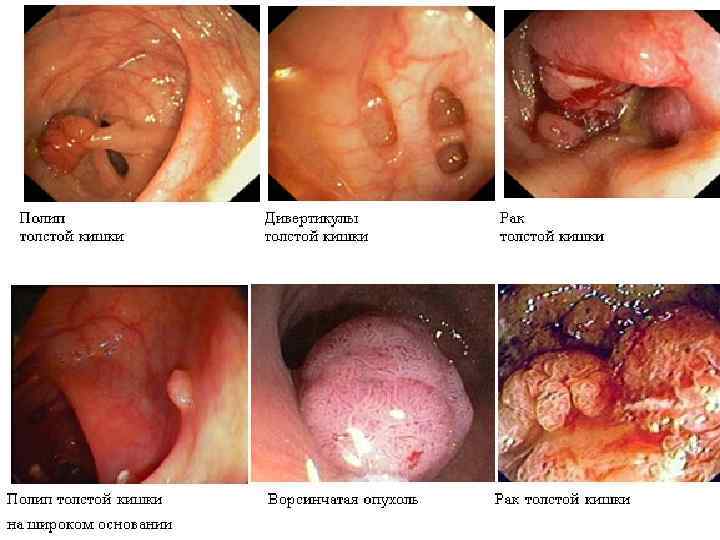

Инструментальная и лабораторная диагностика ОАК – эритроцитоз до 5 6 млн. , лейкоцитоз до 20 тыс. со сдвигом лейкоцитарной формулы влево, эозинопения. , повышение значения СОЭ. БХАК снижение уровня хлоридов с 500— 550 мг% до 400— 300 мг%, повышение остаточного азота, возможно повышение ALT AST CРБ. ОАМ – снижение количественного показателя, повышение концентрации белка. Обзорная рентгенография – наличие «кишечных арок» , «чаши Клойбера» , симптом перистости(растяжение тощей кишки). Ирригоскопия – симптом «трезубца» , видимые нарушения проходимости. Колоноскопия – визуальное определение патологии. УЗИ КТ